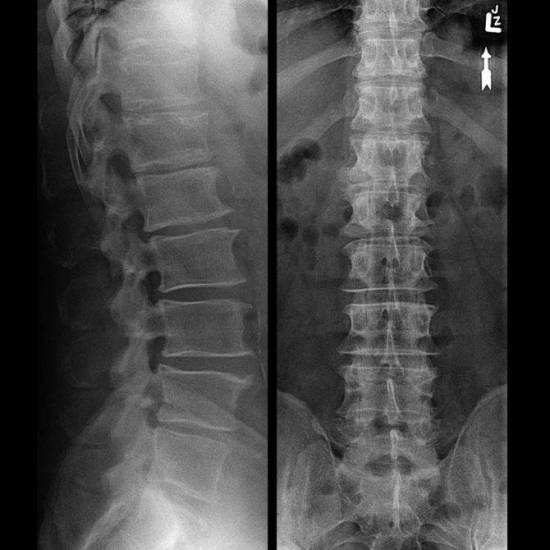

Диагностика спондилоартроза – это стандартная процедура, которая проходит примерно по такой схеме:

Внешний осмотр пациента, пальпация пораженной области. Направление на анализы крови и мочи – результаты помогут установить факт развития воспалительного процесса. Направление на аппаратные исследования – КТ, МРТ, спондилография – методы позволяют определить локализацию поражения, а также степень повреждений, стадию болезни.